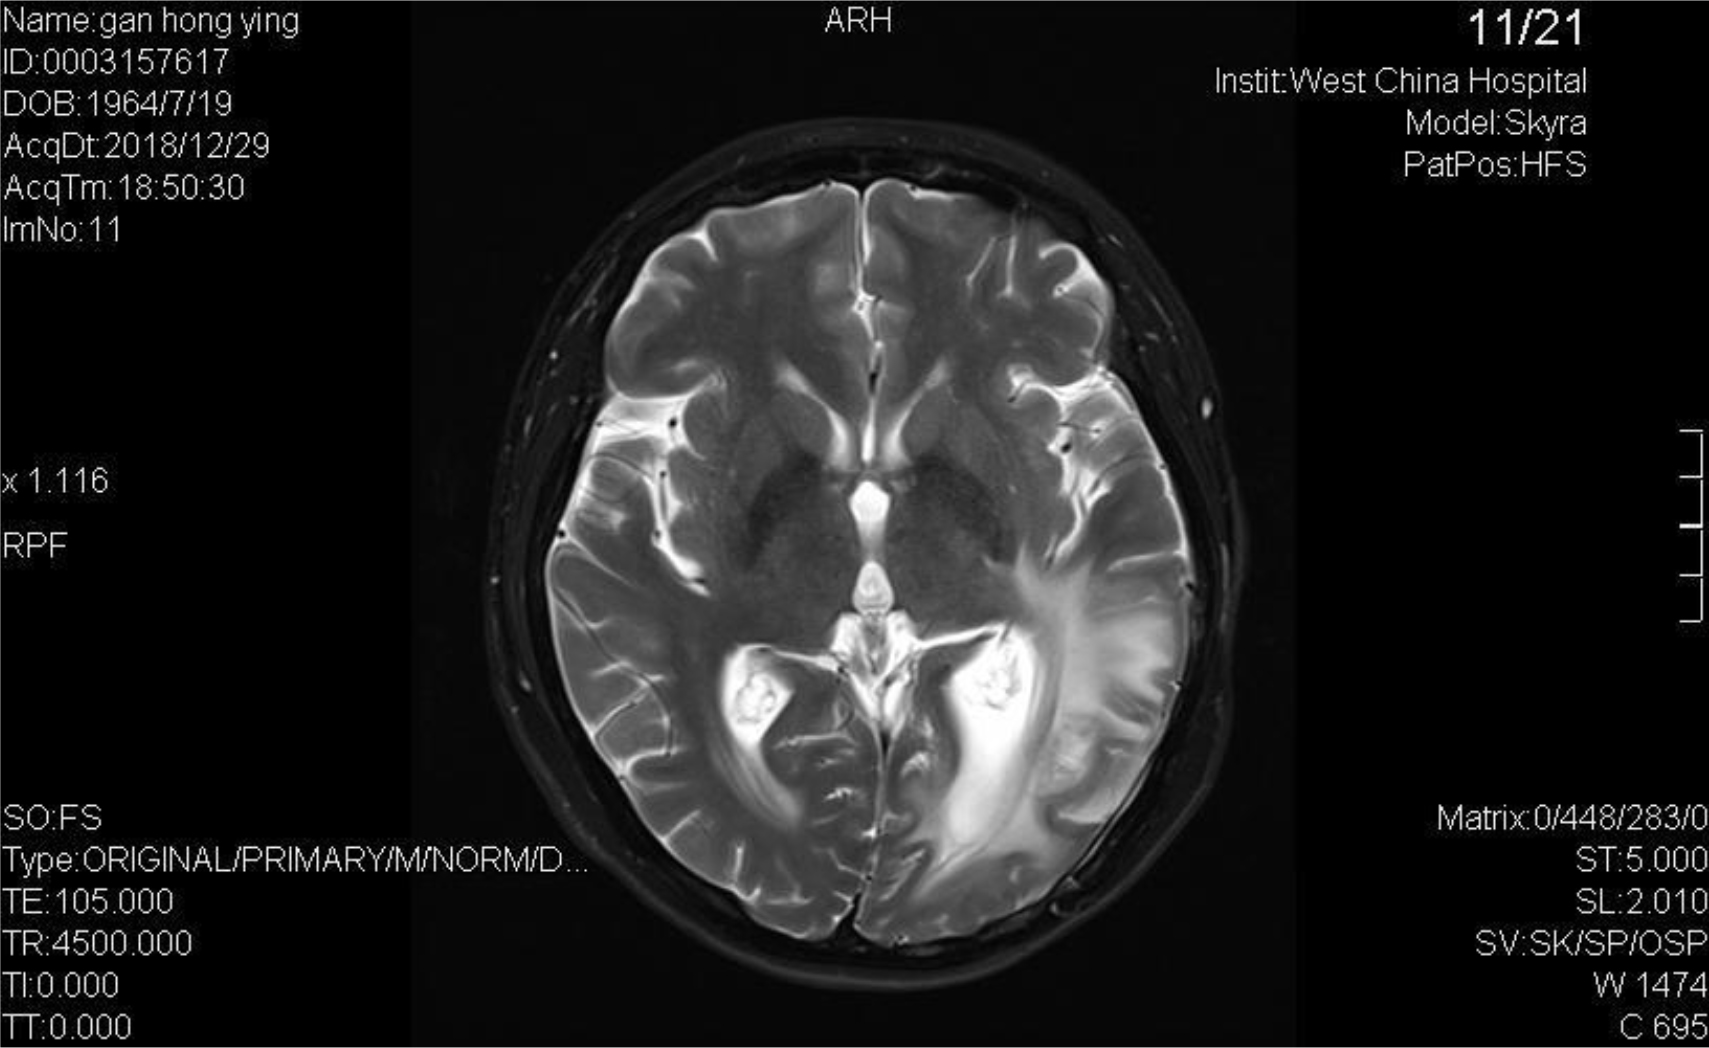

A 54-year-old female, developed a headache in December 2017. Examination showed that the left parietal occipital lobe occupied, and the first surgical treatment was performed, and the postoperative pathological diagnosis was glioblastoma. After operation, the patient received routine radiotherapy, 60Gy/33f, and temozolomide chemotherapy, 100mg/d (during radiotherapy), 300mg d1-5, q4w. In January 2019, the patient reexamined the MRI and found that the left temporal parietal space was occupied (Figure 1) and was operated again. The postoperative pathological diagnosis was still glioblastoma. The patient had occasional headache after operation, and the head MRI examination three months after operation indicated the progress of the disease (Figure 2). TTF was prepared to be used, and finally officially used the TTF treatment on July 4, 2019. The use time was relatively fixed, the utilization rate was 93%, and the compliance was good (Figure 3). During treatment, the patient developed allergic rash scattered on the scalp, mild itching, no ulceration and infection, and recovered quickly after topical application of antiallergic drugs. There had been several times that the patch temperature was too high, and the reasons are as follows: 1. The ambient temperature used was high (e. G. hot weather, direct sunlight, etc.). 2. The contact between the patch and the skin was not good. By instructing the patient to adjust the indoor temperature to about 24 °C, to use the headband or tape to strengthen the loose patch, to use the headband when sleeping at night, and to pay attention to clean the hair of the scalp every time, the situations had been significantly improved. Re-examination of the MRI in October 2019 showed that the condition was stable (Figure 4). Follow-up to 2020.1.23, the patient showed no symptoms of discomfort.

Figure 1